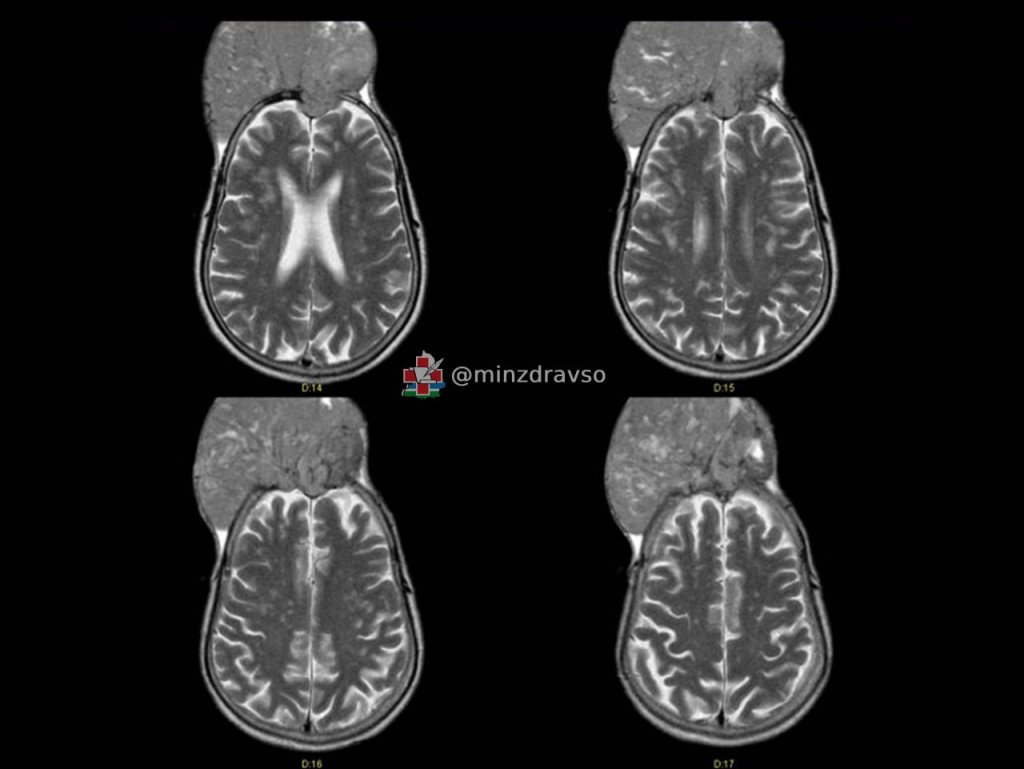

В Свердловском областном онкодиспансере успешно прооперировали жителя Краснотурьинска с редким случаем гигантской доброкачественной опухоли головного мозга (менингиомой), которая разрушила кости черепа и выросла наружу. Об этом сообщает пресс-служба регионального Минздрава.

«Житель Краснотурьинска поступил в отделение нейроонкологии, когда опухоль уже проросла кости черепа и распространилась наружу примерно на 10 сантиметров. При этом она не вызвала никаких симптомов. На вопрос, почему пациент так долго не обращался к врачам, хотя «вторая голова» росла буквально на глазах, мужчина ответить затруднился. В итоге новообразование достигло размеров примерно 15 на 15 сантиметров», – рассказал нейрохирург Свердловского областного онкодиспансера Павел Гвоздев.